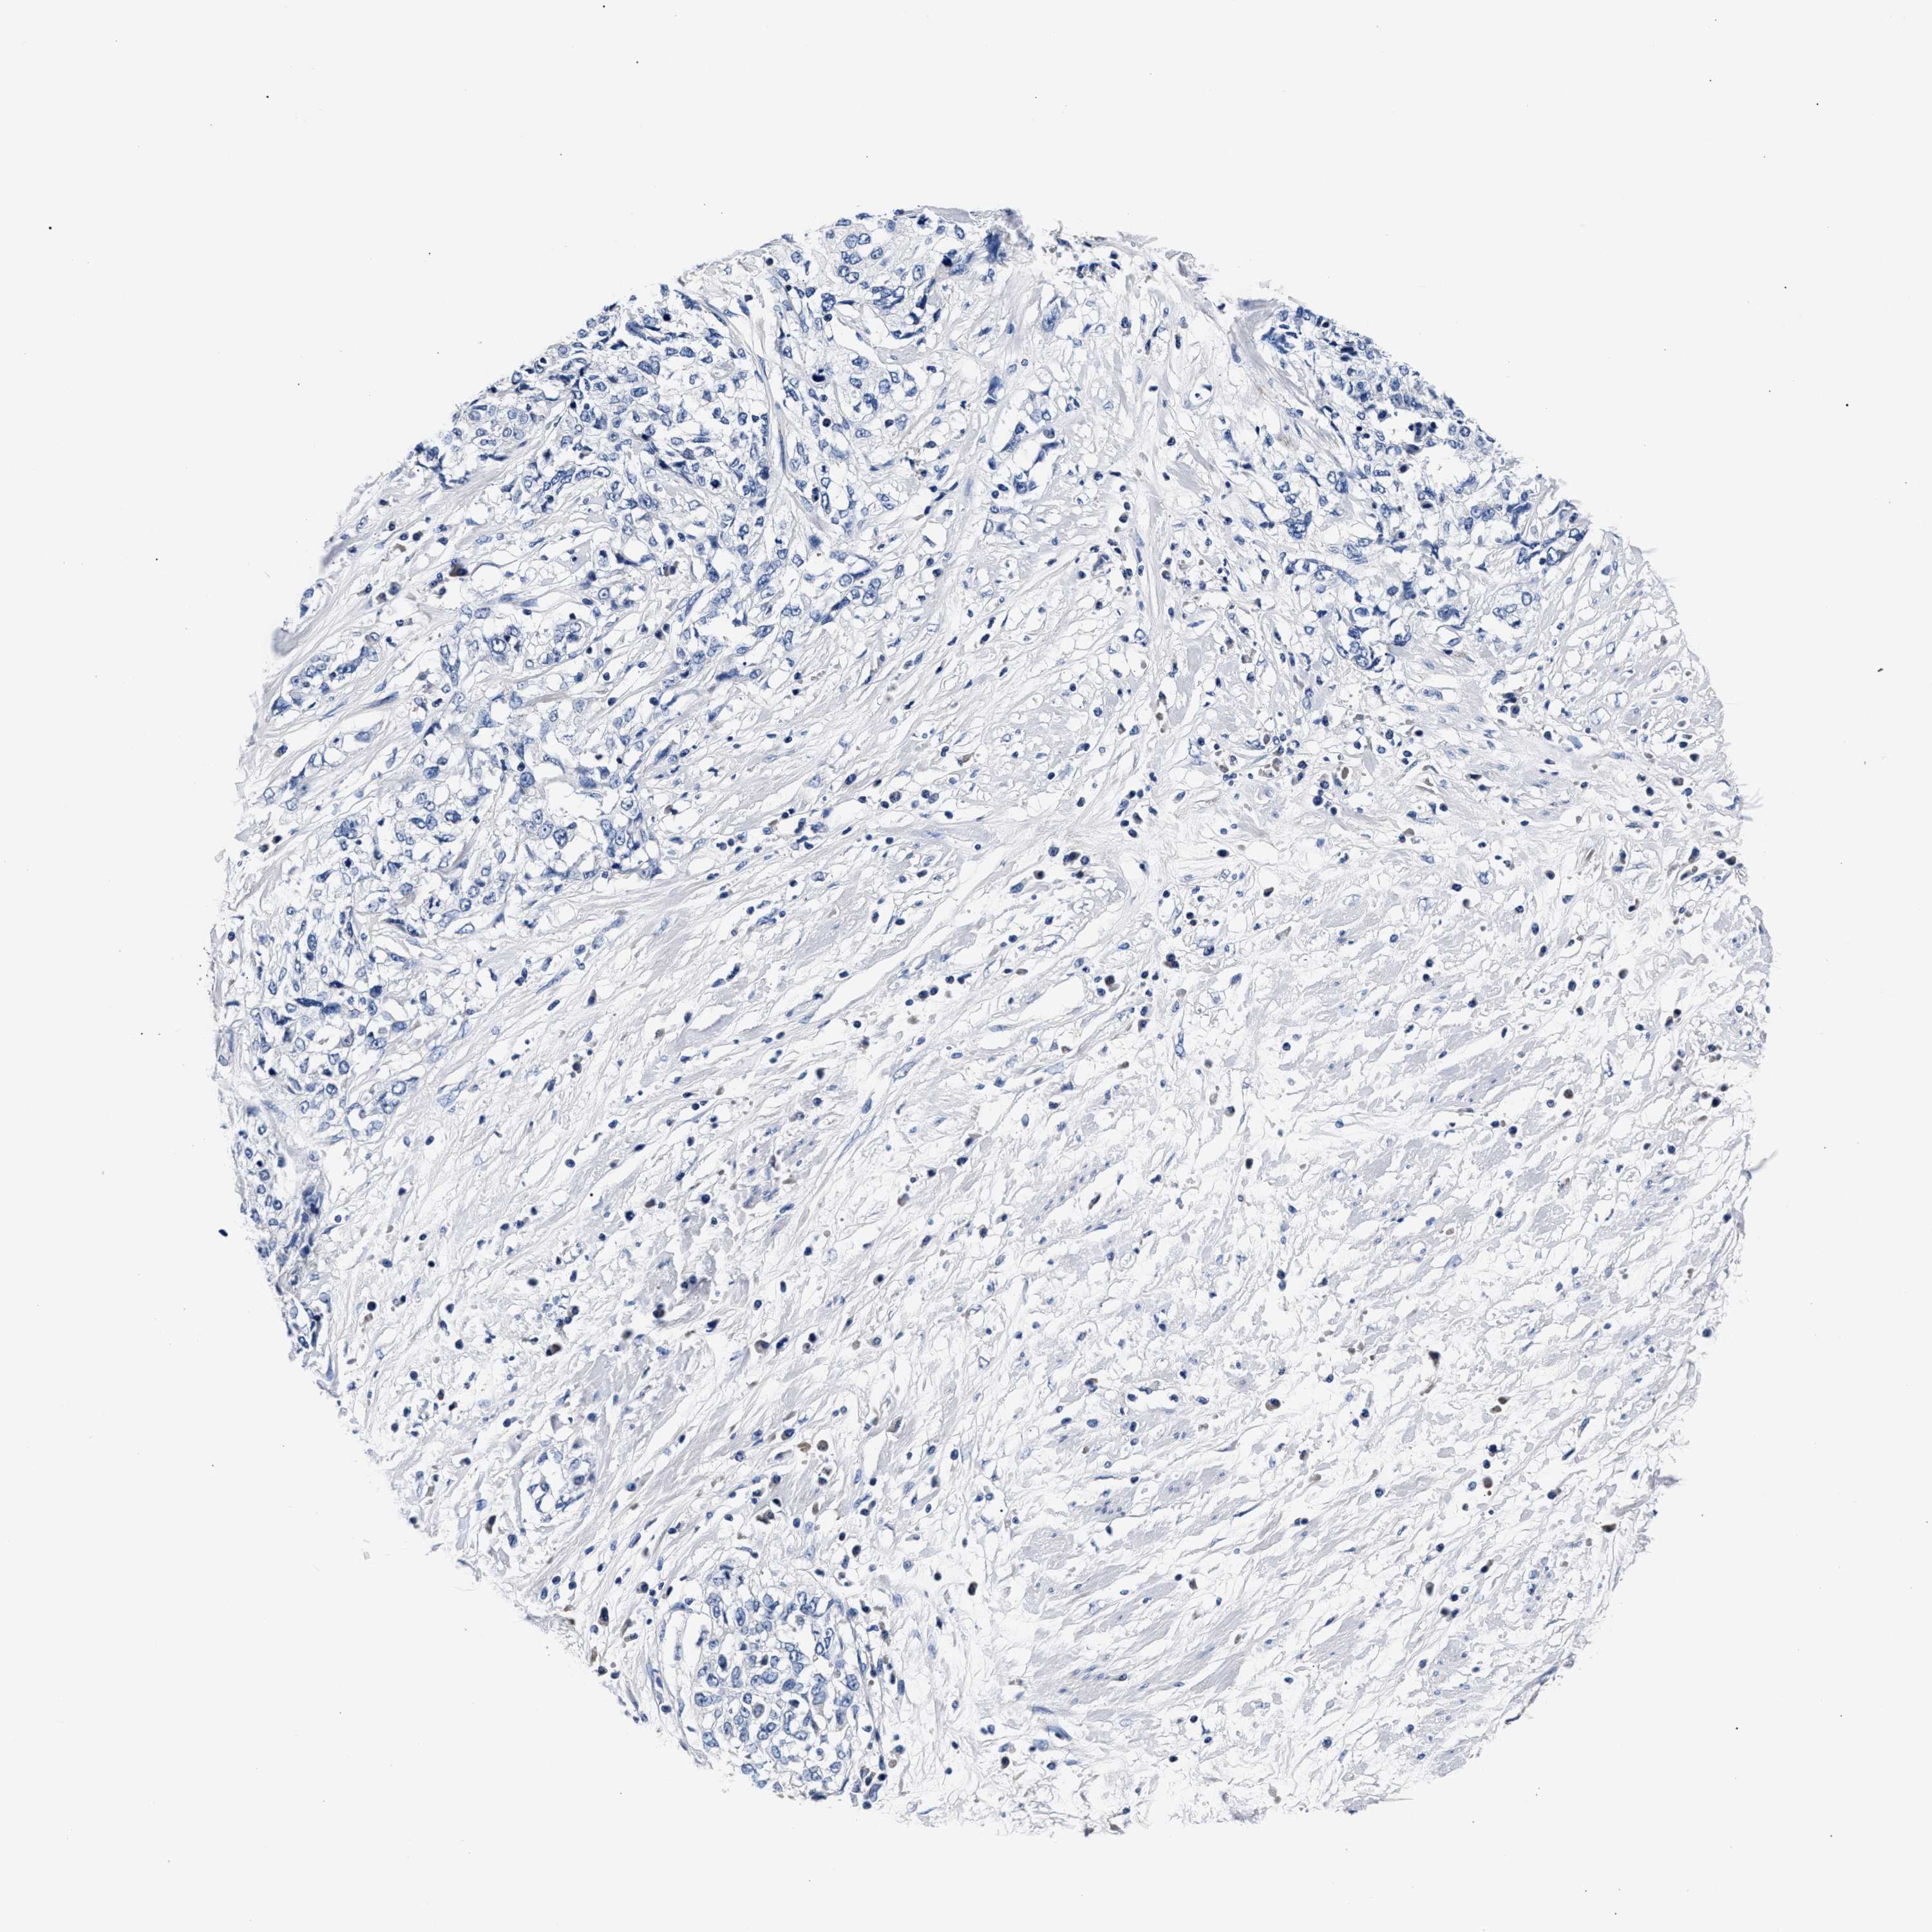

CERVICAL CANCER - Protein expressioni

A mouse-over function shows sample information and annotation data. Click on an image to view it in a full screen mode. Samples can be filtered based on level of antibody staining by selecting one or several of the following categories: high, medium, low and not detected. The assay and annotation is described here.

Note that samples used for immunohistochemistry by the Human Protein Atlas do not correspond to samples in the TCGA dataset.

Antibody stainingi

Antibody staining in the annotated cell types in the current human tissue is reported as not detected, low, medium, or high, based on conventional immunohistochemistry profiling in selected tissues. This score is based on the combination of the staining intensity and fraction of stained cells.

Each image is clickable and will lead to virtual microscopy that enables deeper exploration of all samples and also displays staining intensity scores, fraction scores and subcellular localization as well as patient and tissue information for each sample.

Antibody HPA020974

Staining

High

Medium

Low

Not detected

Intensity

Strong

Moderate

Weak

Negative

Quantity

>75%

75%-25%

<25%

None

Location

Nuclear

Cytoplasmic/membranous

Cytoplasmic/membranous,nuclear

Squamous cell carcinoma, NOS

Adenocarcinoma, NOS